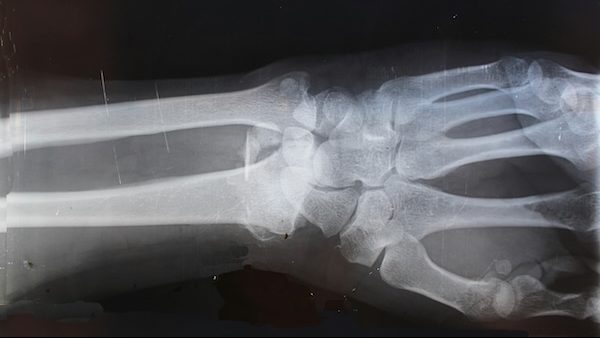

Female athletes are at a much higher risk to tear their ACLs compared to their male counterparts due to a mix of biological and physical factors.

There is a mix of modifiable and non-modifiable aspects that play a part in the difference between male and female risk.

Dr. Mary K. Mulcahey, division director of Sports Medicine at Loyola University highlights that “non-modifiable risk factors, things we cannot change, include gender-related differences in knee anatomy, like the size of the ACL and hormonal fluctuations during the menstrual cycle.”